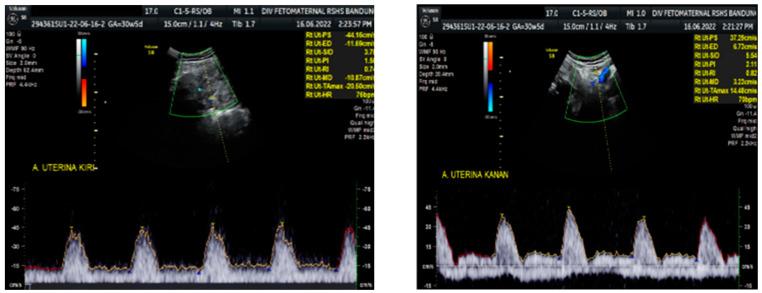

Doppler findings of persistent reverse end-diastolic flow (PREDF) in a fetal middle cerebral artery (MCA) are a very rare sonographic finding and are a marker of poor fetal condition. This finding often leads to intrauterine fetal death or early neonatal death. Reverse end-diastolic flow in the middle cerebral artery is an advanced hemodynamic event. Fetal cerebral circulation normally has a high impedance; in the event of fetal hypoxemia, impedance decreases, resulting in the central redistribution of blood flow to vital organs, which maintains the oxygen delivery to the brain. Reverse flow in the middle cerebral arteries describes the loss of this autoregulatory process. PREDF is a sequence that occurs due to increased extracranial or intracranial pressure. Previous case reports mentioned intracranial hemorrhage, fetal growth restriction, fetal anemia, and fetal hepatic abnormalities as problems leading to PREDF. This condition presumably arises due to cerebral edema associated with severe hypoxemia. We reported Doppler findings of PREDF MCA in a 33-year-old female patient at 30 weeks gestation who was referred to the hospital with severe preeclampsia accompanied by fetal growth restriction and oligohydramnios. A cesarean section was performed due to severe preeclampsia and a low bishop score. Hypotheses on various etiologies and their association with intrauterine/neonatal death as well as the best management still require further investigation.

胎儿大脑中动脉(MCA)中持续出现反向舒张末期血流(REDF)的多普勒发现是一种非常罕见的超声表现,是胎儿状况不佳的标志。这一发现常导致宫内胎儿死亡或新生儿早期死亡。大脑中动脉的反向舒张末期血流是一种高级的血液动力学事件。胎儿脑循环通常具有较高的阻抗;在胎儿缺氧的情况下,阻抗降低,导致血流向重要器官的中央重新分布,从而维持向大脑输送氧气。大脑中动脉的反向血流描述了这种自动调节过程的丧失。REDF 是由于颅外或颅内压增加而发生的一系列现象。之前的病例报告提到颅内出血、胎儿生长受限、胎儿贫血和胎儿肝脏异常是导致 PREDF 的问题。这种情况可能是由于严重缺氧引起的脑水肿所致。我们报告了一例 33 岁女性患者在 30 孕周时的 MCA PREDF 多普勒发现,该患者因严重子痫前期伴胎儿生长受限和羊水过少而被转诊入院。由于严重子痫前期和低 Bishop 评分而行剖宫产术。各种病因及其与宫内/新生儿死亡的关联,以及最佳治疗方法仍需要进一步研究。